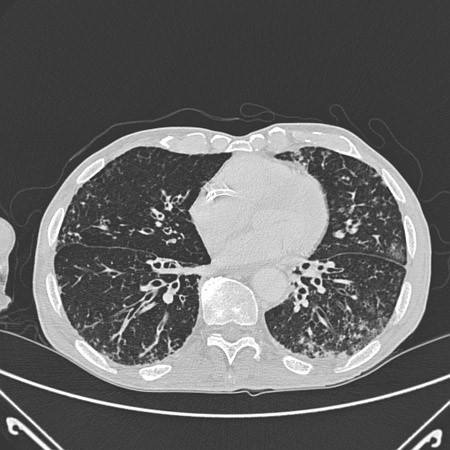

• High-resolution CT imaging of the chest to look for bronchiectasis (which does not always promote a productive cough), foreign body aspiration, pulmonary fibrosis, or other structural lung disease (which may not show well on chest x-ray). Chronic suppurative lung disease is diagnosed in patients with clinical symptoms of bronchiectasis but no radiographic evidence of bronchiectasis.[50] CT imaging may also indicate the presence of an aortic aneurysm or Zenker’s diverticulum. The diagnostic yield of the CT scan of the chest in a patient with chronic cough and normal chest x-ray is expected to be low.[3][Evidence C] There is no high-quality evidence to support the use of chest CT in the initial evaluation of patients presenting with chronic cough.[38]

[Figure caption and citation for the preceding image starts]: Chest CT with presence of signet ring on left in a patient with bronchiectasisFrom the personal collection of Dr S.M. Bhorade, University of Chicago Medical Center [Citation ends].com.bmj.content.model.assessment.Caption@769db40d[Figure caption and citation for the preceding image starts]: Chest CT with dilated and thickened airways and peripheral tree-in-bud pattern in a patient with bronchiectasisFrom the personal collection of Dr S.M. Bhorade, University of Chicago Medical Center; used with permission [Citation ends].com.bmj.content.model.assessment.Caption@5d8c3fb7[Figure caption and citation for the preceding image starts]: Chest CT showing idiopathic pulmonary fibrosisFrom the personal collection of Dr J.C. Munson, Center for Clinical Epidemiology and Biostatistics, University of Pennsylvania School of Medicine [Citation ends].com.bmj.content.model.assessment.Caption@43159570[Figure caption and citation for the preceding image starts]: Chest CT of a patient with amiodarone pulmonary toxicity, showing asymmetrical opacities with a peripheral distributionFrom the personal collection of Dr A. Pataka and Professor P. Argyropoulou, Aristotle University, Thessaloniki, Greece [Citation ends].com.bmj.content.model.assessment.Caption@33fbbbbd[Figure caption and citation for the preceding image starts]: CT of the chest with intravenous contrast material showing complete left lower lobe collapse with a radiopaque object within the left lower main bronchus surrounded by a halo of airBMJ Case Reports 2008 (doi:10.1136/bcr.06.2008.0013). Copyright 2008 BMJ Publishing Group Ltd [Citation ends].com.bmj.content.model.assessment.Caption@72dca222[Figure caption and citation for the preceding image starts]: Bronchoscopy image showing a loquat seed completely occluding the bronchus intermediusFrom the personal collection of Dr S. Murgu and Dr H. Colt, University of California at Irvine Medical Center [Citation ends].com.bmj.content.model.assessment.Caption@18215d6d